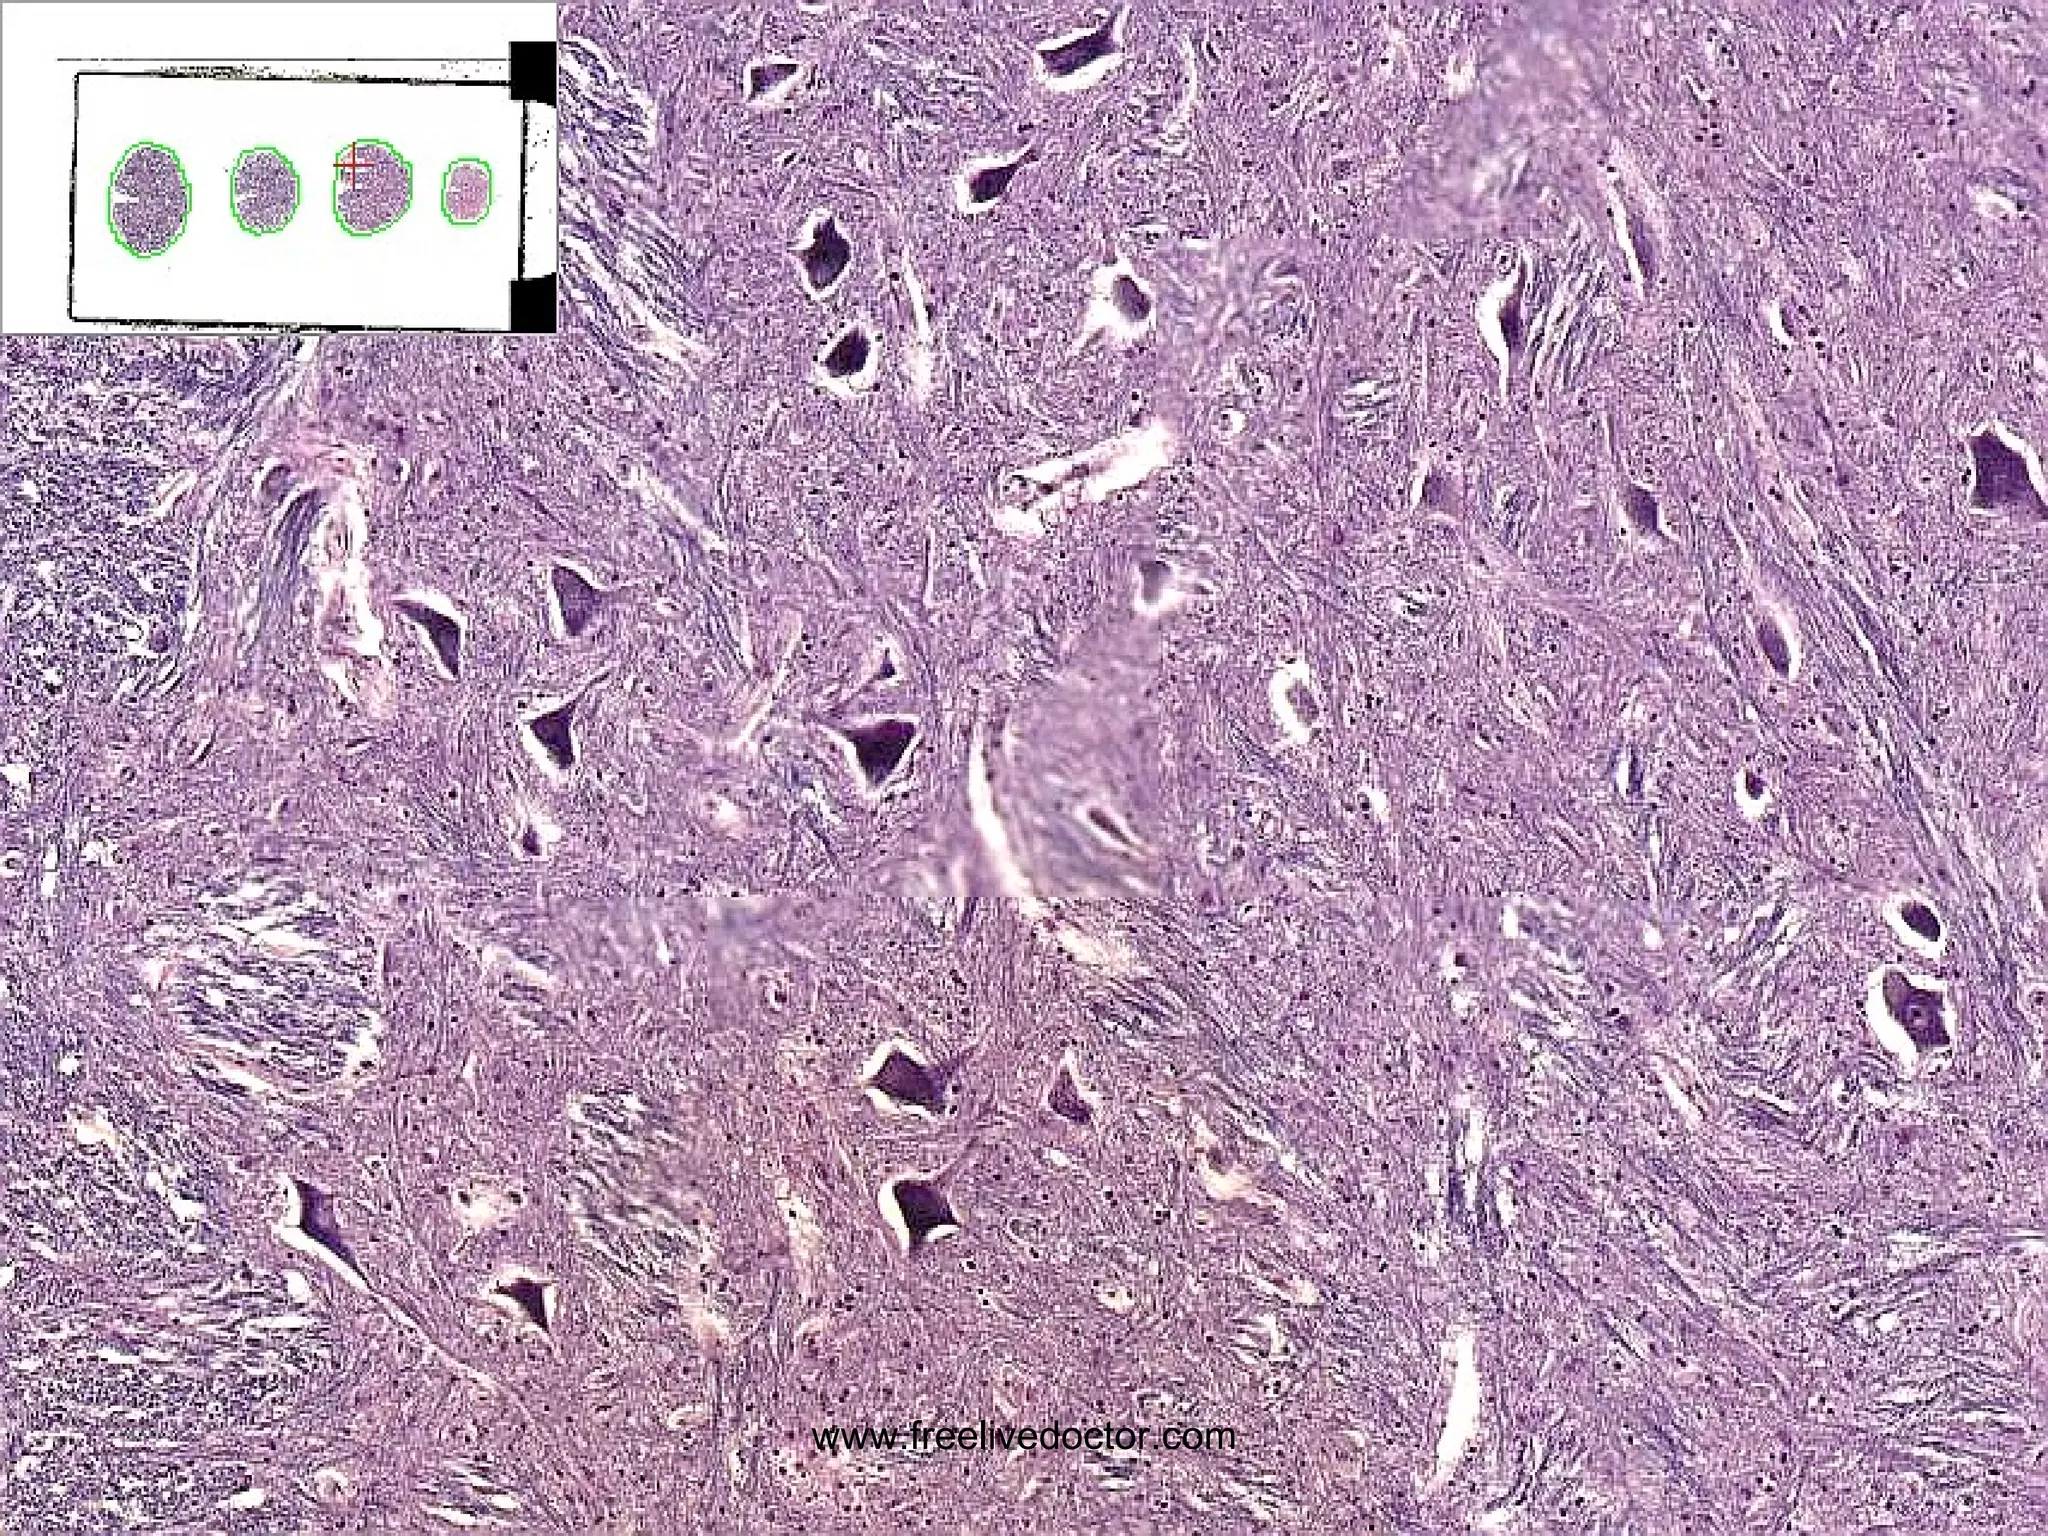

• #152 Gliosis vs. Glioma?

• #153 Glioma, intermediate grade